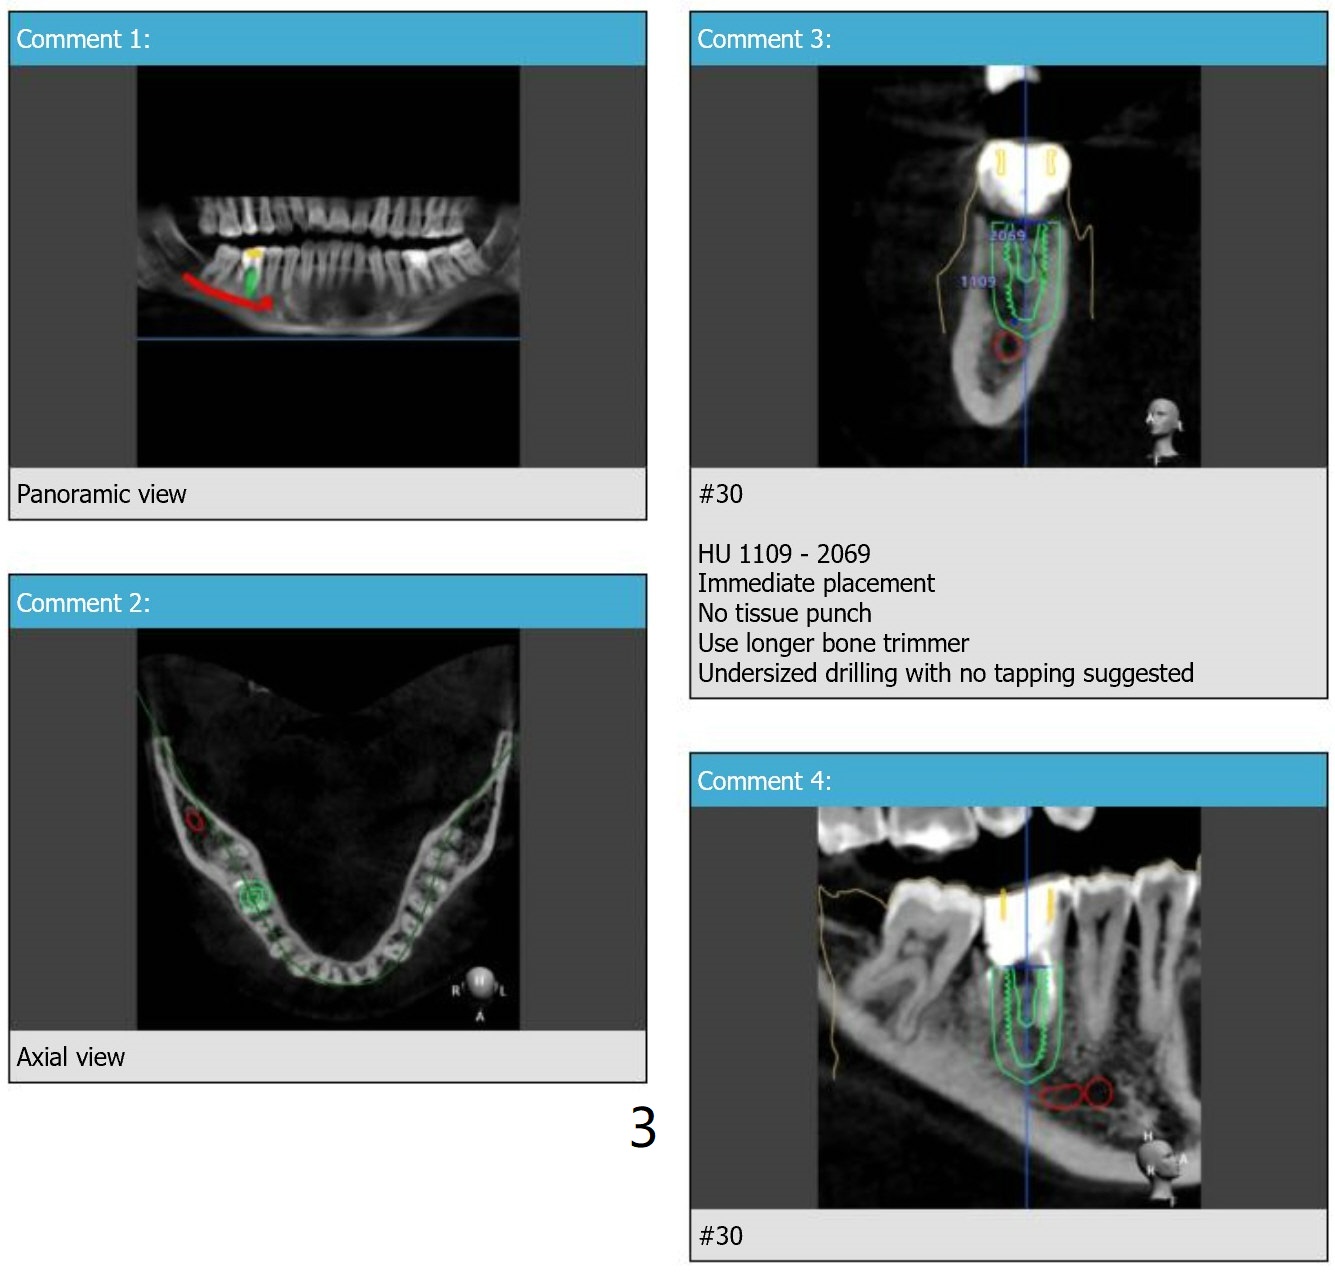

Longer Implant

A 11.5 mm long implant will be placed to increase primary stability because of the large mesial apical lesion.